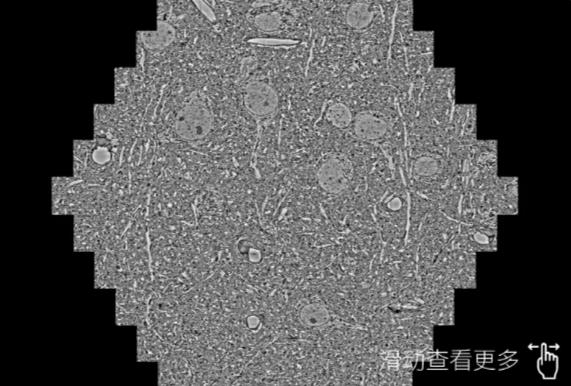

鼠脑切片。左图使用那曲蔡司那曲扫描电镜MultiSEM706对165μmx143pm面积区域成像,耗时仅需1.5秒。右图为鼠脑切片中30μm区域放大效果。样品由芝加哥大学B.Kasthuri提供。

使用蔡司高速那曲扫描电镜MultiSEM对1mm²人脑皮层组织进行高分辨成像,并对其中的各种细胞结构进行三维重构分析。左图展示了2x3mm²组织平面中锥体神经元的三维重构效果。右图显示了局部体积神经元三维重构。图像由哈佛大学chtman实验室提供,渲染图由D. Berger 制作。